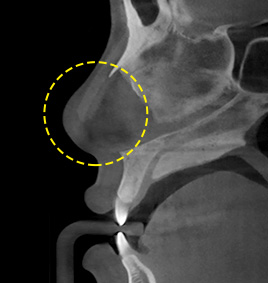

CASE 2Aquiline nose curved in the middle

The bone and cartilage are appropriately removed depending on the degree of the curve.